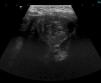

Presentamos el caso de un niño de 6 años que cursó con un cuadro brusco de vómitos y dolor abdominal con ecografía sugestiva de invaginación (fig. 1).